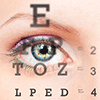

Blackmores 澳佳宝 Macu-Vision 叶黄素护眼 90片

$31.99 $39.99

Blackmores 澳佳宝 叶黄素护眼片 保护视力 45片

$26.99 $35.00

Blackmores 澳佳宝叶黄素护眼胶囊 高级版 60粒

$30.99 $40.99